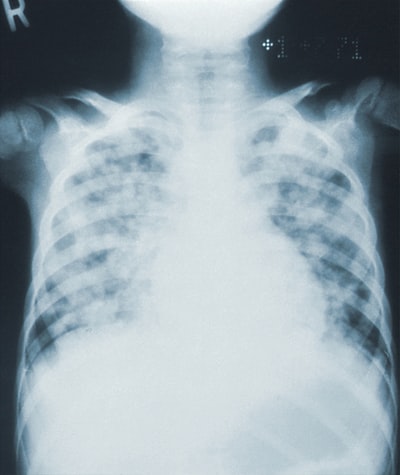

どちらも両肺に広範なすりガラス影や浸潤影を伴います。

もう少し詳しく読み込むと、以下のようなポイントの違いがあります。

ARDS

- 下肺優位

- 胸膜直下まで均等分布

- 左肺優位の胸水

- 肺血管腫大なし

- spared lobule(汎小葉性辺縁陰影中の正常に見える所見;病理では異常所見を伴う)

心原性肺水腫

- 上肺優位

- 再外層の胸膜直下への分布が少ない

- 右側優位の胸水

- 肺血管の腫大、小葉間隔壁の肥厚

- 心拡大や上縦隔の拡大